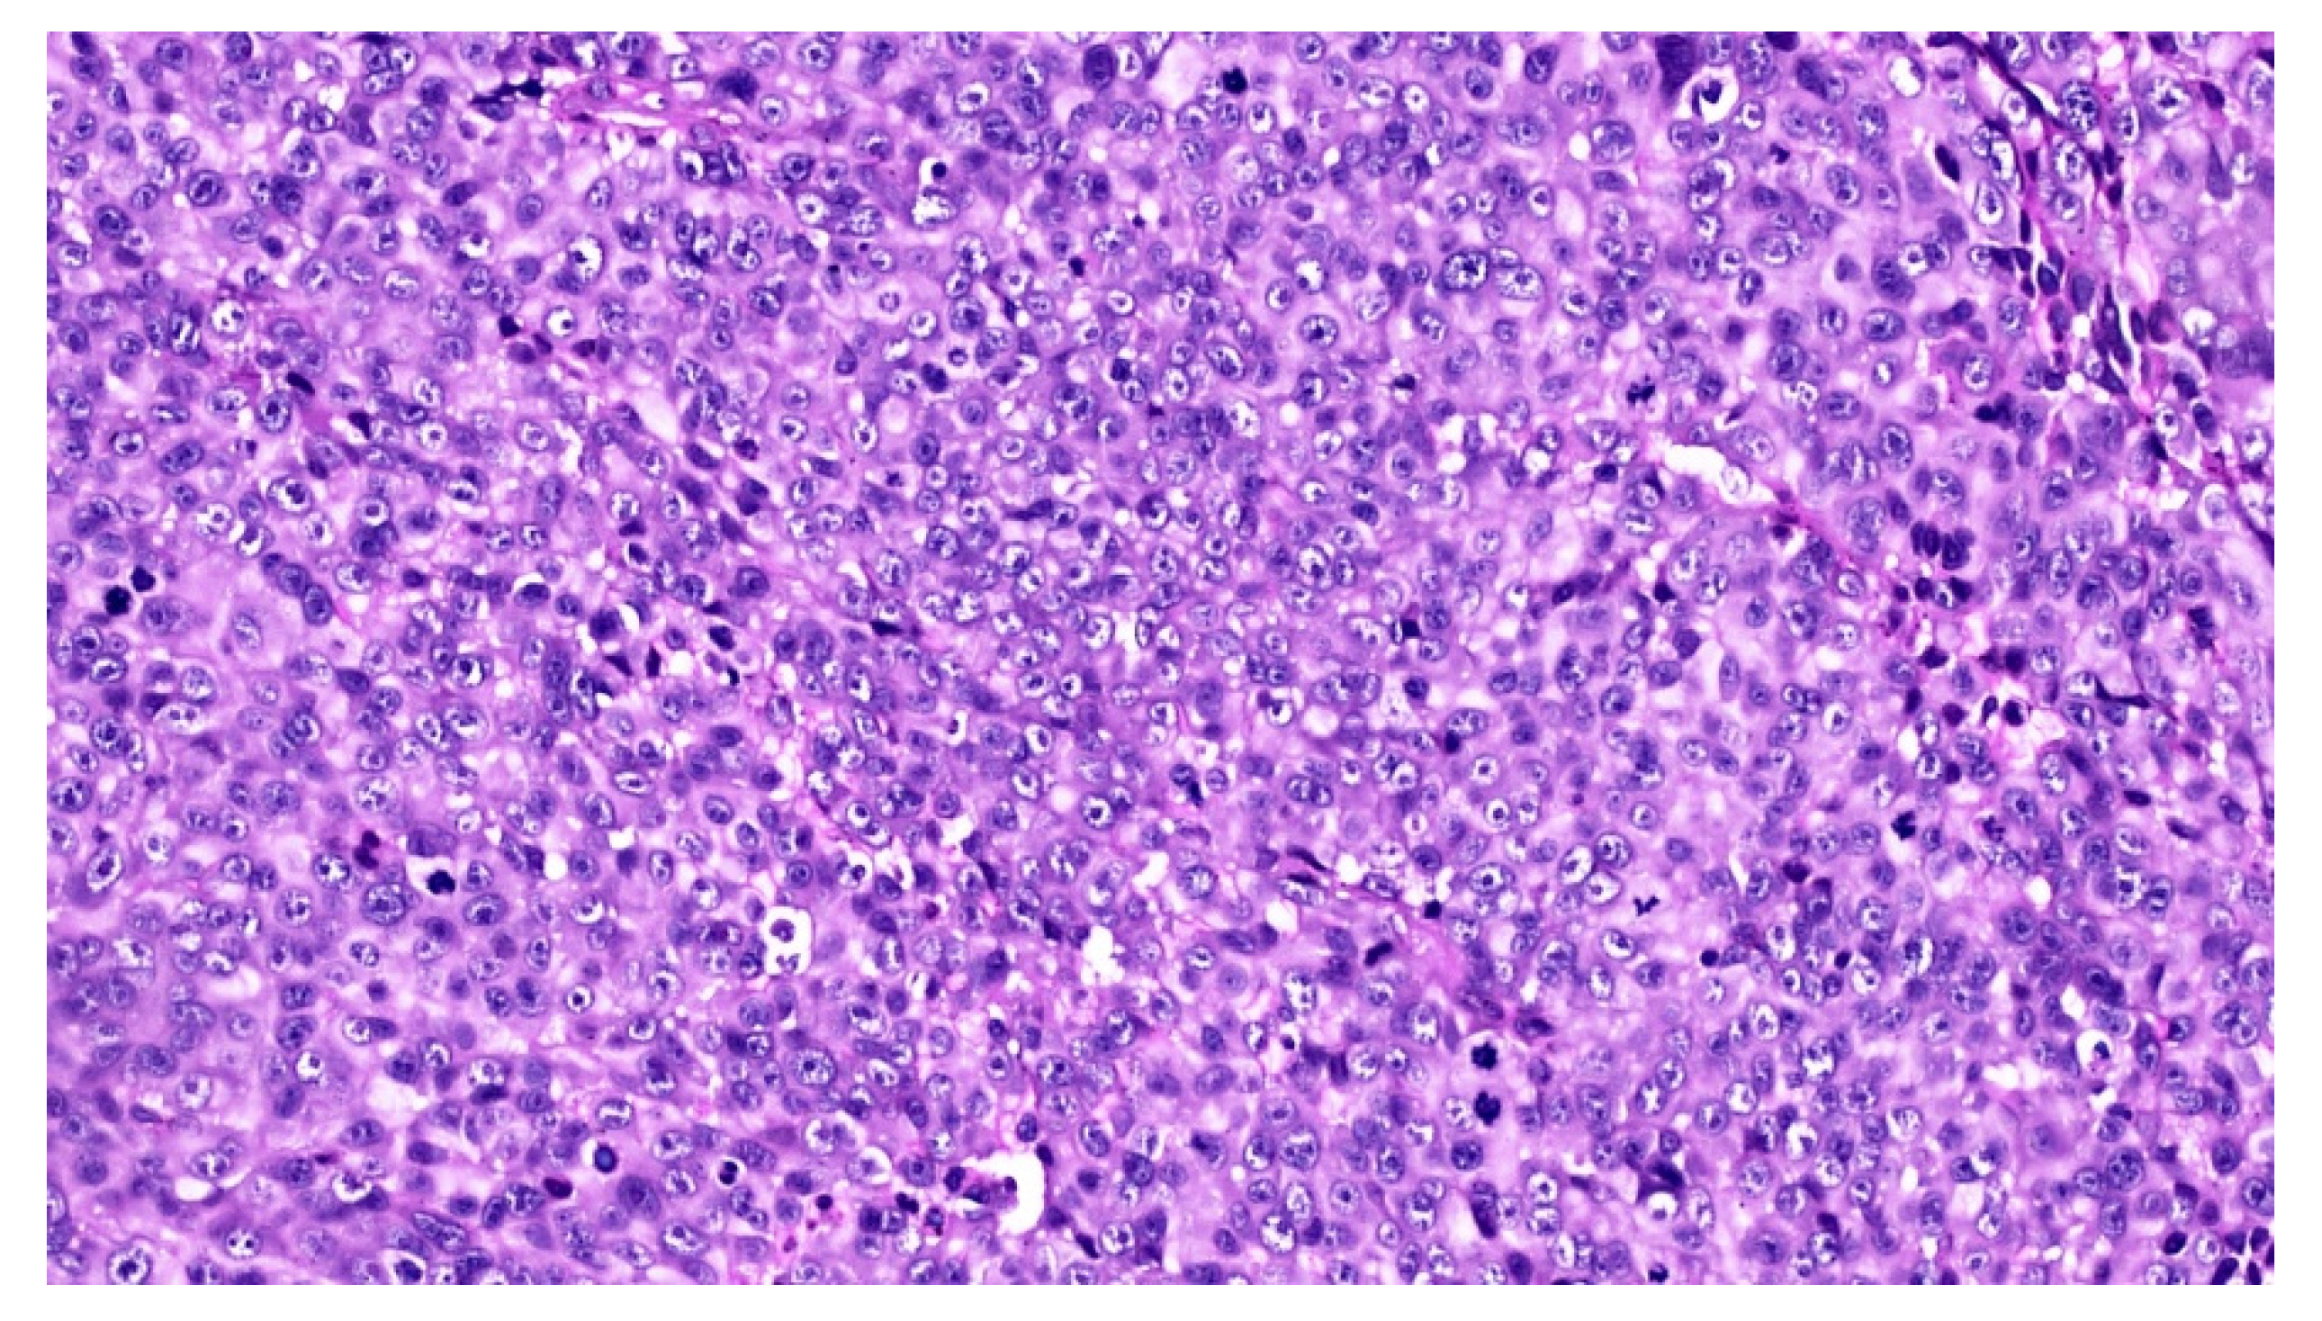

An incisional biopsy of the mass was performed in an area without pigmentation, and the tissue fragment sent for histopathologic examination. Microscopically, the hematoxylin and eosin stained sections revealed a fragment of oral mucosa, lined by keratinized and hypotrophic stratified squamous epithelium (Figure 4), and a dense proliferation of spindle-shaped and epithelioid neoplastic cells in the lamina propria. The tumor cells displayed pleomorphic nuclei with prominent nucleoli and evident mitotic activity (Figure 5). Neoplastic junctional proliferation was detected in some areas.

Figure 5.

The tumor cells are epithelioid in shape, amelanotic and arranged in nests or nodules (Hematoxylin & Eosin, ×20).